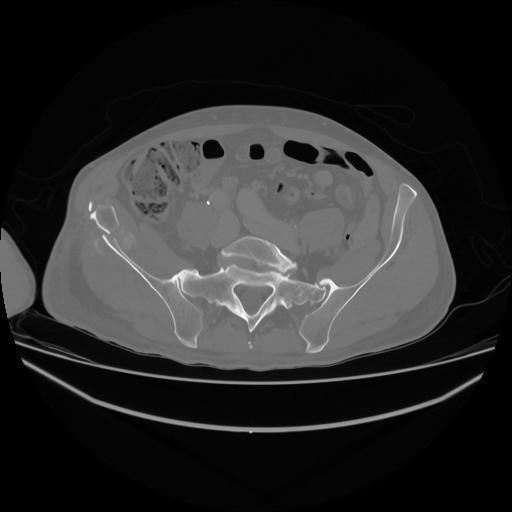

5 CUERPO,CE,Vol,1.0,CUERPO,,